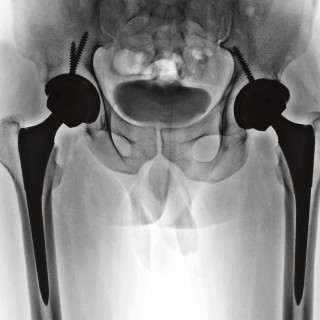

Kirurgens kjønn har ingen betydning for dødeligheten etter operasjon. De eldste kirurgene har best resultater. Det viser en ny studie. Påvirker kirurgens alder eller kjønn utfallet for pasienten? I en ny studie publisert i tidsskriftet BMJ ble over 890 000 akuttopererte pasienter over 65 år inkludert (1). Operasjonene ble utført av mer enn 45 000 kirurger i perioden 2011–14. Dødeligheten var noe økt blant pasienter behandlet av kirurger under 40 år (6,6 %, 95 % KI 6,5–6,7) sammenlignet med dem over 60 år (6,3 %, 95 % KI 6,2–6,5) etter justering for bl.a. tilstandens alvorlighetsgrad. Kirurgens...